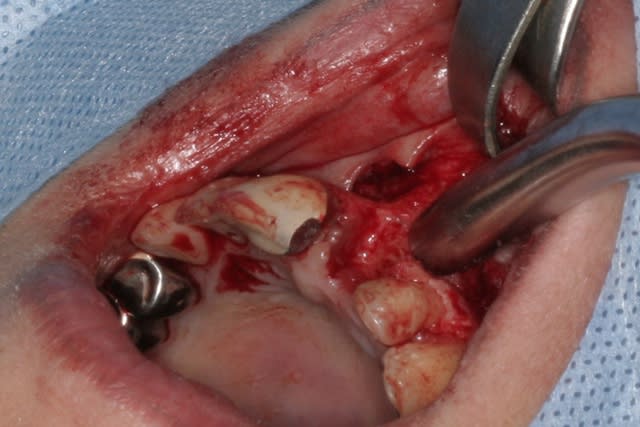

tien, ce matin, extraction de 24/25, curetage méticuleux, forage, comblement du gap, pose des 2 implants qui se sont bloqués à 50Ncm au CA sur les 3 ou 4 mm apicaux, pose des vis de cicat, sutures...35min....tranquille...

un autre cas EII MCI sur 11/21...mais en photos (j'ai aussi la vidéo, faut que je la passe sur youtube)